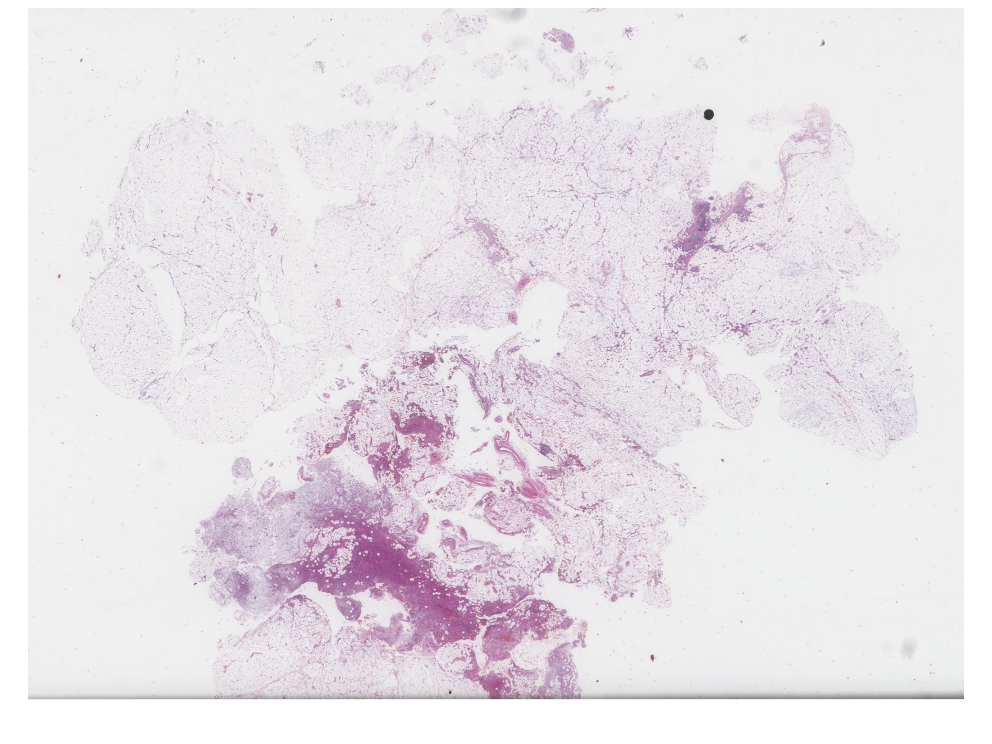

66.1 Case-1

Mikroskopik görüntüleri inceleyin:

İntradermal Nodüler Fasciitis